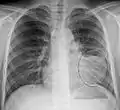

AP CXR showing left lower lobe pneumonia associated with a small left sided pleural effusion

AP CXR showing right lower lobe pneumonia

AP CXR showing pneumonia of the lingula of the left lung

Right upper lobe pneumonia as marked by the circle.

Left upper lobe pneumonia with a small pleural effusion.

Right lower lobe pneumonia as seen on a lateral CXR